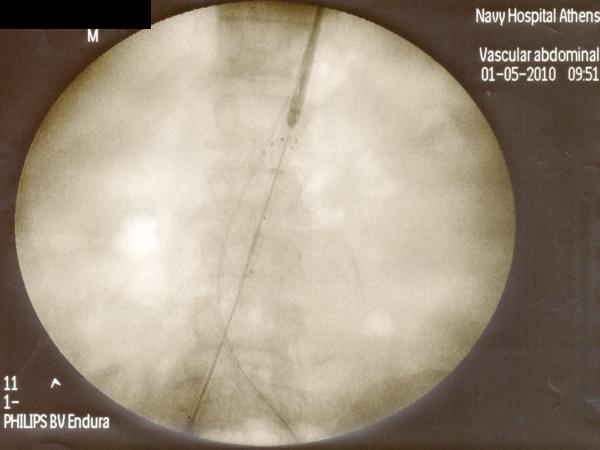

Ενδαγγειακή αποκατάσταση ανευρυσμάτων κοιλιακής αορτής

12ο Πανελλήνιο Συνέδριο Αγγειακής και Ενδαγγειακής Χειρουργικής

2010, Αθήνα